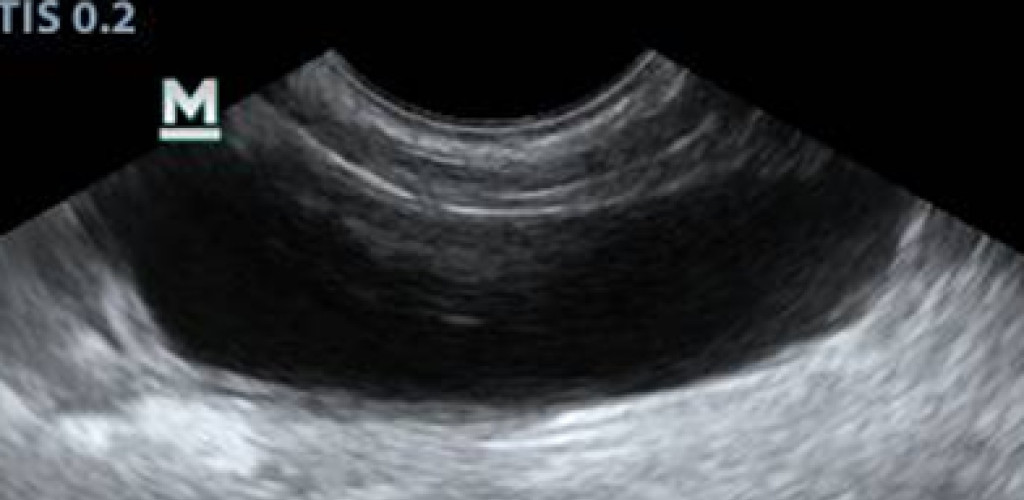

УЗИ после лечения у животных не выявило наличия патологий: мочевой пузырь овоидной формы лоцировался топографически правильно. Его объем варьировался в зависимости от степени наполнения мочой. Содержимое мочевого пузыря анэхогенной природы, мелкодисперсная взвесь, как правило, отсутствовала. Размер его стенки был меньше по сравнению с данными до лечения (рис. 6).